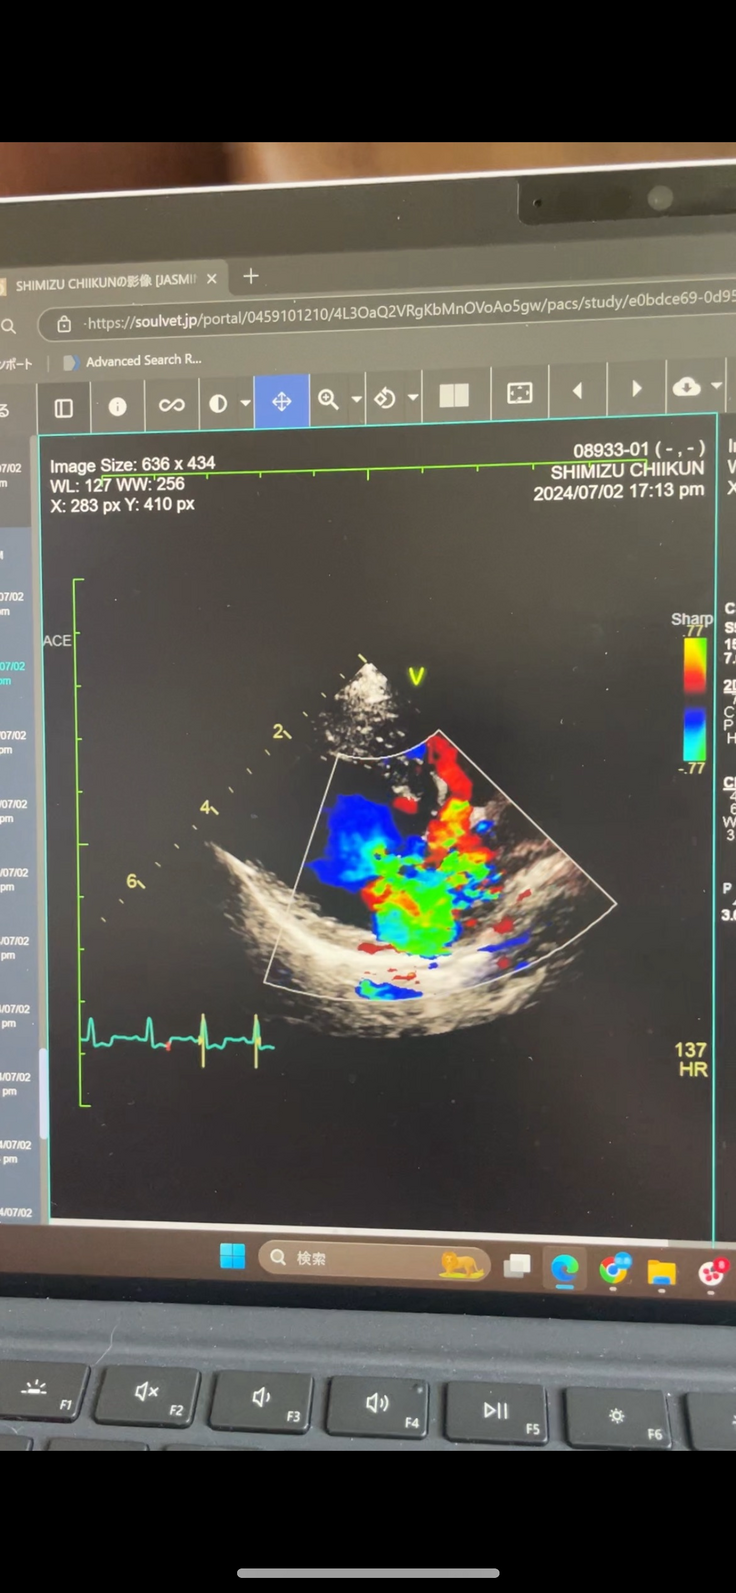

手術前のエコー写真(7月)↓↓↓

手術前のエコーと比べるとほんとに良くなってるなと感じます